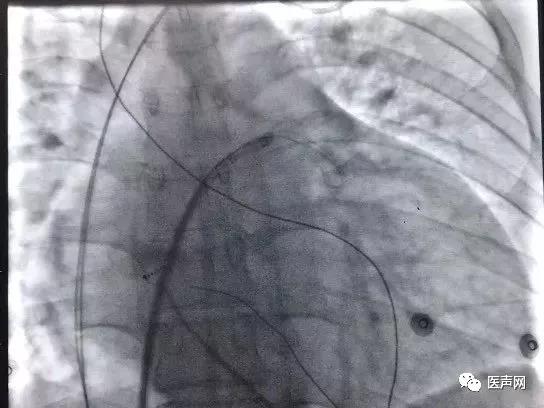

将撤出的导丝调转方向(软头朝前)经该自股动脉造影导管重新送至右心房,下腔静脉。经锁骨下静脉可撕开长鞘送入圈套器,于下腔静脉中抓捕导丝后从锁骨下静脉拉出体外。

沿导丝送入可撕开长鞘至左室,送入导线(2088TC 65cm)至三维标测指定的靶向位点,经测试,阈值0.5V,螺旋固定。